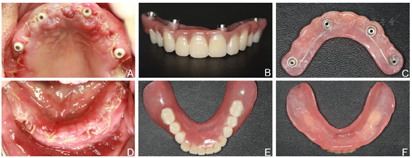

(3)术后1周,制取上颌种植基台水平印模及下颌无牙颌印模,制作蜡堤记录上下颌颌位关系,采用息止颌位法确定垂直距离,吞咽咬合法确定水平关系,转移颌位关系后,当日制作上颌种植体支持式固定义齿及下颌可摘总义齿过渡修复(图6)。上颌修复至第二前磨牙,下颌修复至第一磨牙,调整咬合接触,戴牙后2周、1个月复诊,下颌义齿组织面重衬、调牙合后义齿稳定。

(6)制作终义齿:下颌种植术后6个月(2016年7月),取下上下颌固定过渡义齿,制取复合基台水平硅橡胶印模,利用过渡义齿记录上下颌位关系、上牙合架,排牙,试排牙,CAD/CAM技术制作钛支架,采用树脂基托及人工牙完成终义齿,上下颌修复至第一磨牙。戴入后调整咬合,上下颌中线居中、对称,露齿线、唇颊面部丰满度患者满意(图11、图12)。